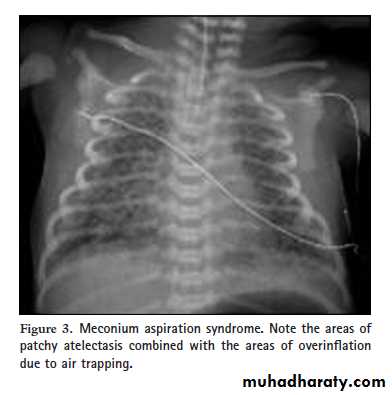

Chest x-ray:- Patchy infiltrates, overdistention , flattening of diaphragm, increase anteroposterior diameter& high incidence of pneumomediastinum& pneumothorax.

Meconium aspiration. The radiograph reveals irregularly distributed areas of hyperaeration and consolidation.